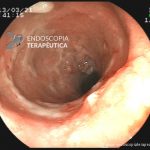

- Doença de Crohn em remissão – pseudopólipo